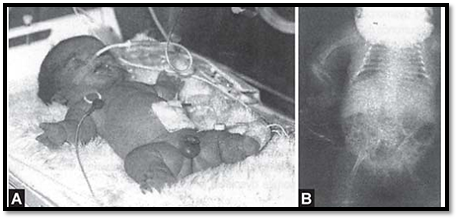

Dysplasia

The term dysplasia is applied to an abnormal organization of cells in a tissue and usually affects all parts of the body where that particular tissue is present. An example is thanatophoric dysplasia, which is a type of skeletal dysplasia, which occurs due to mutations in FGFR3 gene (Figs 5A and B). Here all parts of the skeleton are affected. In ectodermal dysplasia, tissues of ectodermal origin like hair, teeth and nails are involved. Most dysplasias occur as a result of single gene defect, and have a high recurrence risk for siblings and children.

Figs 5A and B: (A) Skeletal dysplasia in a new born (B) X-rays of the same infant showing shortening of the long bones and narrow thoracic cavity